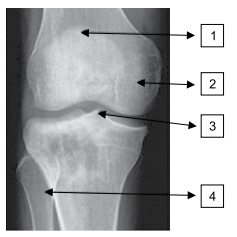

As estruturas assinaladas correspondem a qual alternativa?